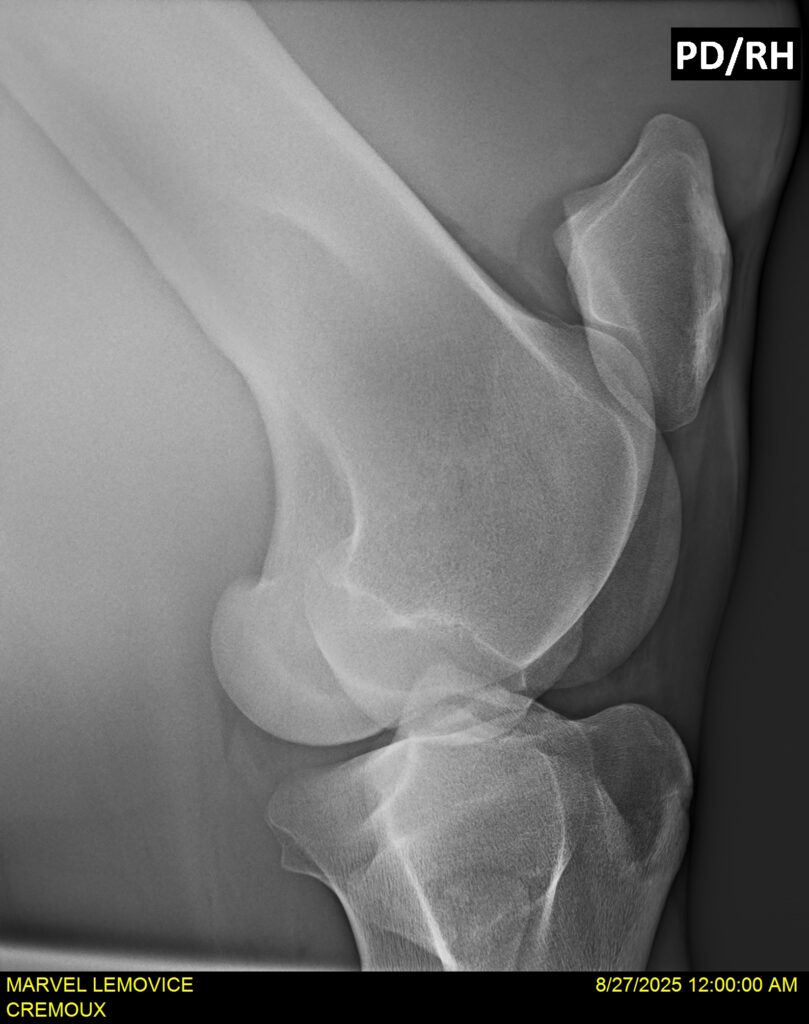

MARVEL LEMOVICE, hongre, Selle Français prend 4 ans en 2026. POPSTAR LOZONAIS x ROSIRE sur une excellente souche maternelle de l’élevage PLATIERE. Débourré aux trois allures et mise en route à l’obstacle. Super modèle avec du cadre et de la force, cheval respectueux avec des moyens. Très agréable au quotidien. Transport OK, maréchalerie OK, santé RAS, Bilan 20 clichés radios + clinique OK.

RADIOS ET CLINIQUE